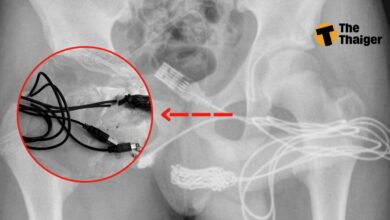

หมอช็อก! เจอสาย USB ติดอยู่ในไอจ้อน ของเด็ก 15 อ้างทำเพื่อวัดขนาด

เมื่อวันที่ 7 กันยายน 2565 สื่อนอกอย่าง DailyStar ได้มีรายงานพบเด็กชายอายุ 15 ปีชาวอังกฤษ ไม่ปรากฏชื่อ-นามสกุล ต้องเข้ารับการรักษาด่วนที่โรงพยาบาล เนื่องจากอาการเจ็บที่องคชาติอย่างรุ่นแรง หลังจากการเอ